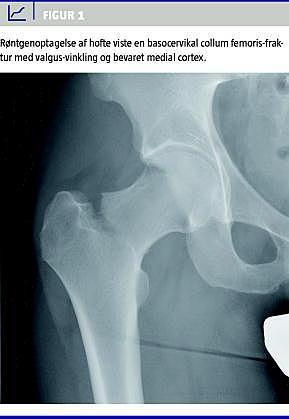

Der blev taget røntgenbillede af højre hofte i to planer, der viste en basocervikal collum femoris-fraktur med valgus-vinkling og bevaret medial cortex (Figur 1 ).